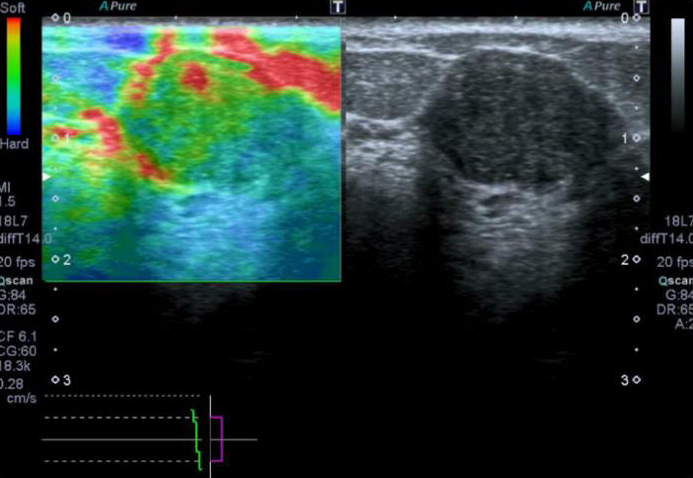

ShearWave Elastography 기능이 탑재되어 질병 의심 부위의 탄성도 차이를 측정하여 종괴의 단단한 정도를 알 수 있습니다.